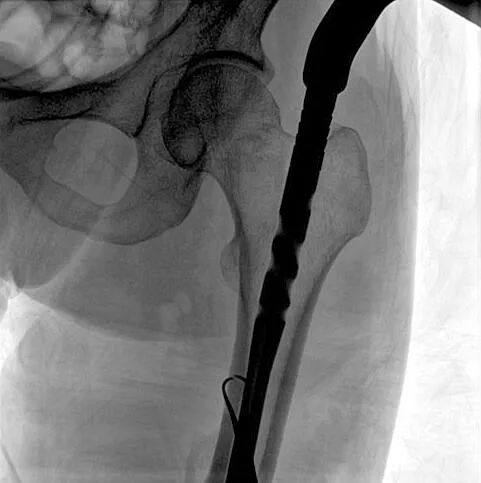

術中使用普愛醫療大平板一體式C形臂進行透視,判斷骨折情況及克氏針、髓內釘等金屬植入物的位置,進行調整。C形臂準確的術中定位,大大縮短了手術的時間,減輕了患者的痛苦,輔助手術順利完成。

在進行髓內釘內固定術時,醫生需要同時觀察到入釘點和骨折部位的情況,普愛醫療大平板一體式C形臂采用30CM×30CM的平板探測器,能夠呈現更廣闊的成像面積,滿足大部分長骨髓內釘內固定術的攝片需求。

術中定位準確、出血量少,術后影像顯示股骨移位糾正,恢復良好力線,手術效果良好。